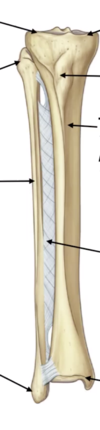

Label the parts of the tibia and fibula on the diagram